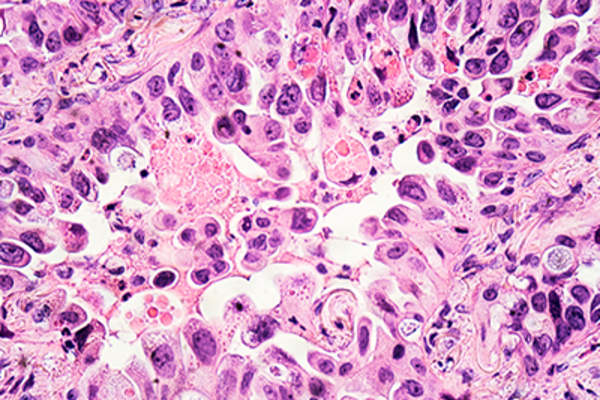

腺癌

腺癌是NSCLC的三种主要亚型之一,是生长在器官内壁的任何一种癌症,通常生长在产生分泌物的细胞中。腺癌是最常见的肺癌类型,在所有肺癌患者中仅占50%以上。它生长在肺泡的内层,在产生粘液的细胞中。

大细胞癌

NSCLC的三个主要亚型的至少普遍的,大细胞癌生长在肺部的内衬;约10 NSCLC的诊断的百分比被称为大细胞。它的特点是,它生长在通常比大多数肺细胞大细胞的事实。

鳞状细胞癌

其中非小细胞肺癌,鳞状细胞癌(又称表皮样癌)的三个主要亚型的约占25所有肺癌的百分比。它生长在小的,扁平的鳞状细胞衬肺的内表面上。